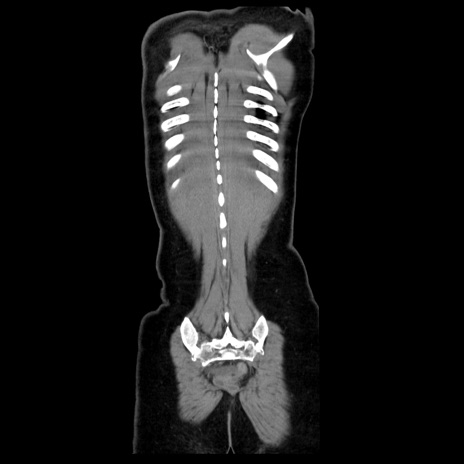

症例39(冠状断像)

【症例】40歳代女性

【主訴】上下腹部痛

【現病歴】2日目から下腹部痛あり。夜間は痛みで眠れなかった。昨日より上腹部痛と下痢が出現。臥位で痛みは軽快したため、休んでいた。本日になって臥位でも立位でも痛みが強くなってきたため救急要請。

【既往歴】子宮内膜症

【身体所見】部:平坦・軟、左上下腹部に圧痛あり、反跳痛あり。

【データ】WBC 21800、CRP 26.78

CT